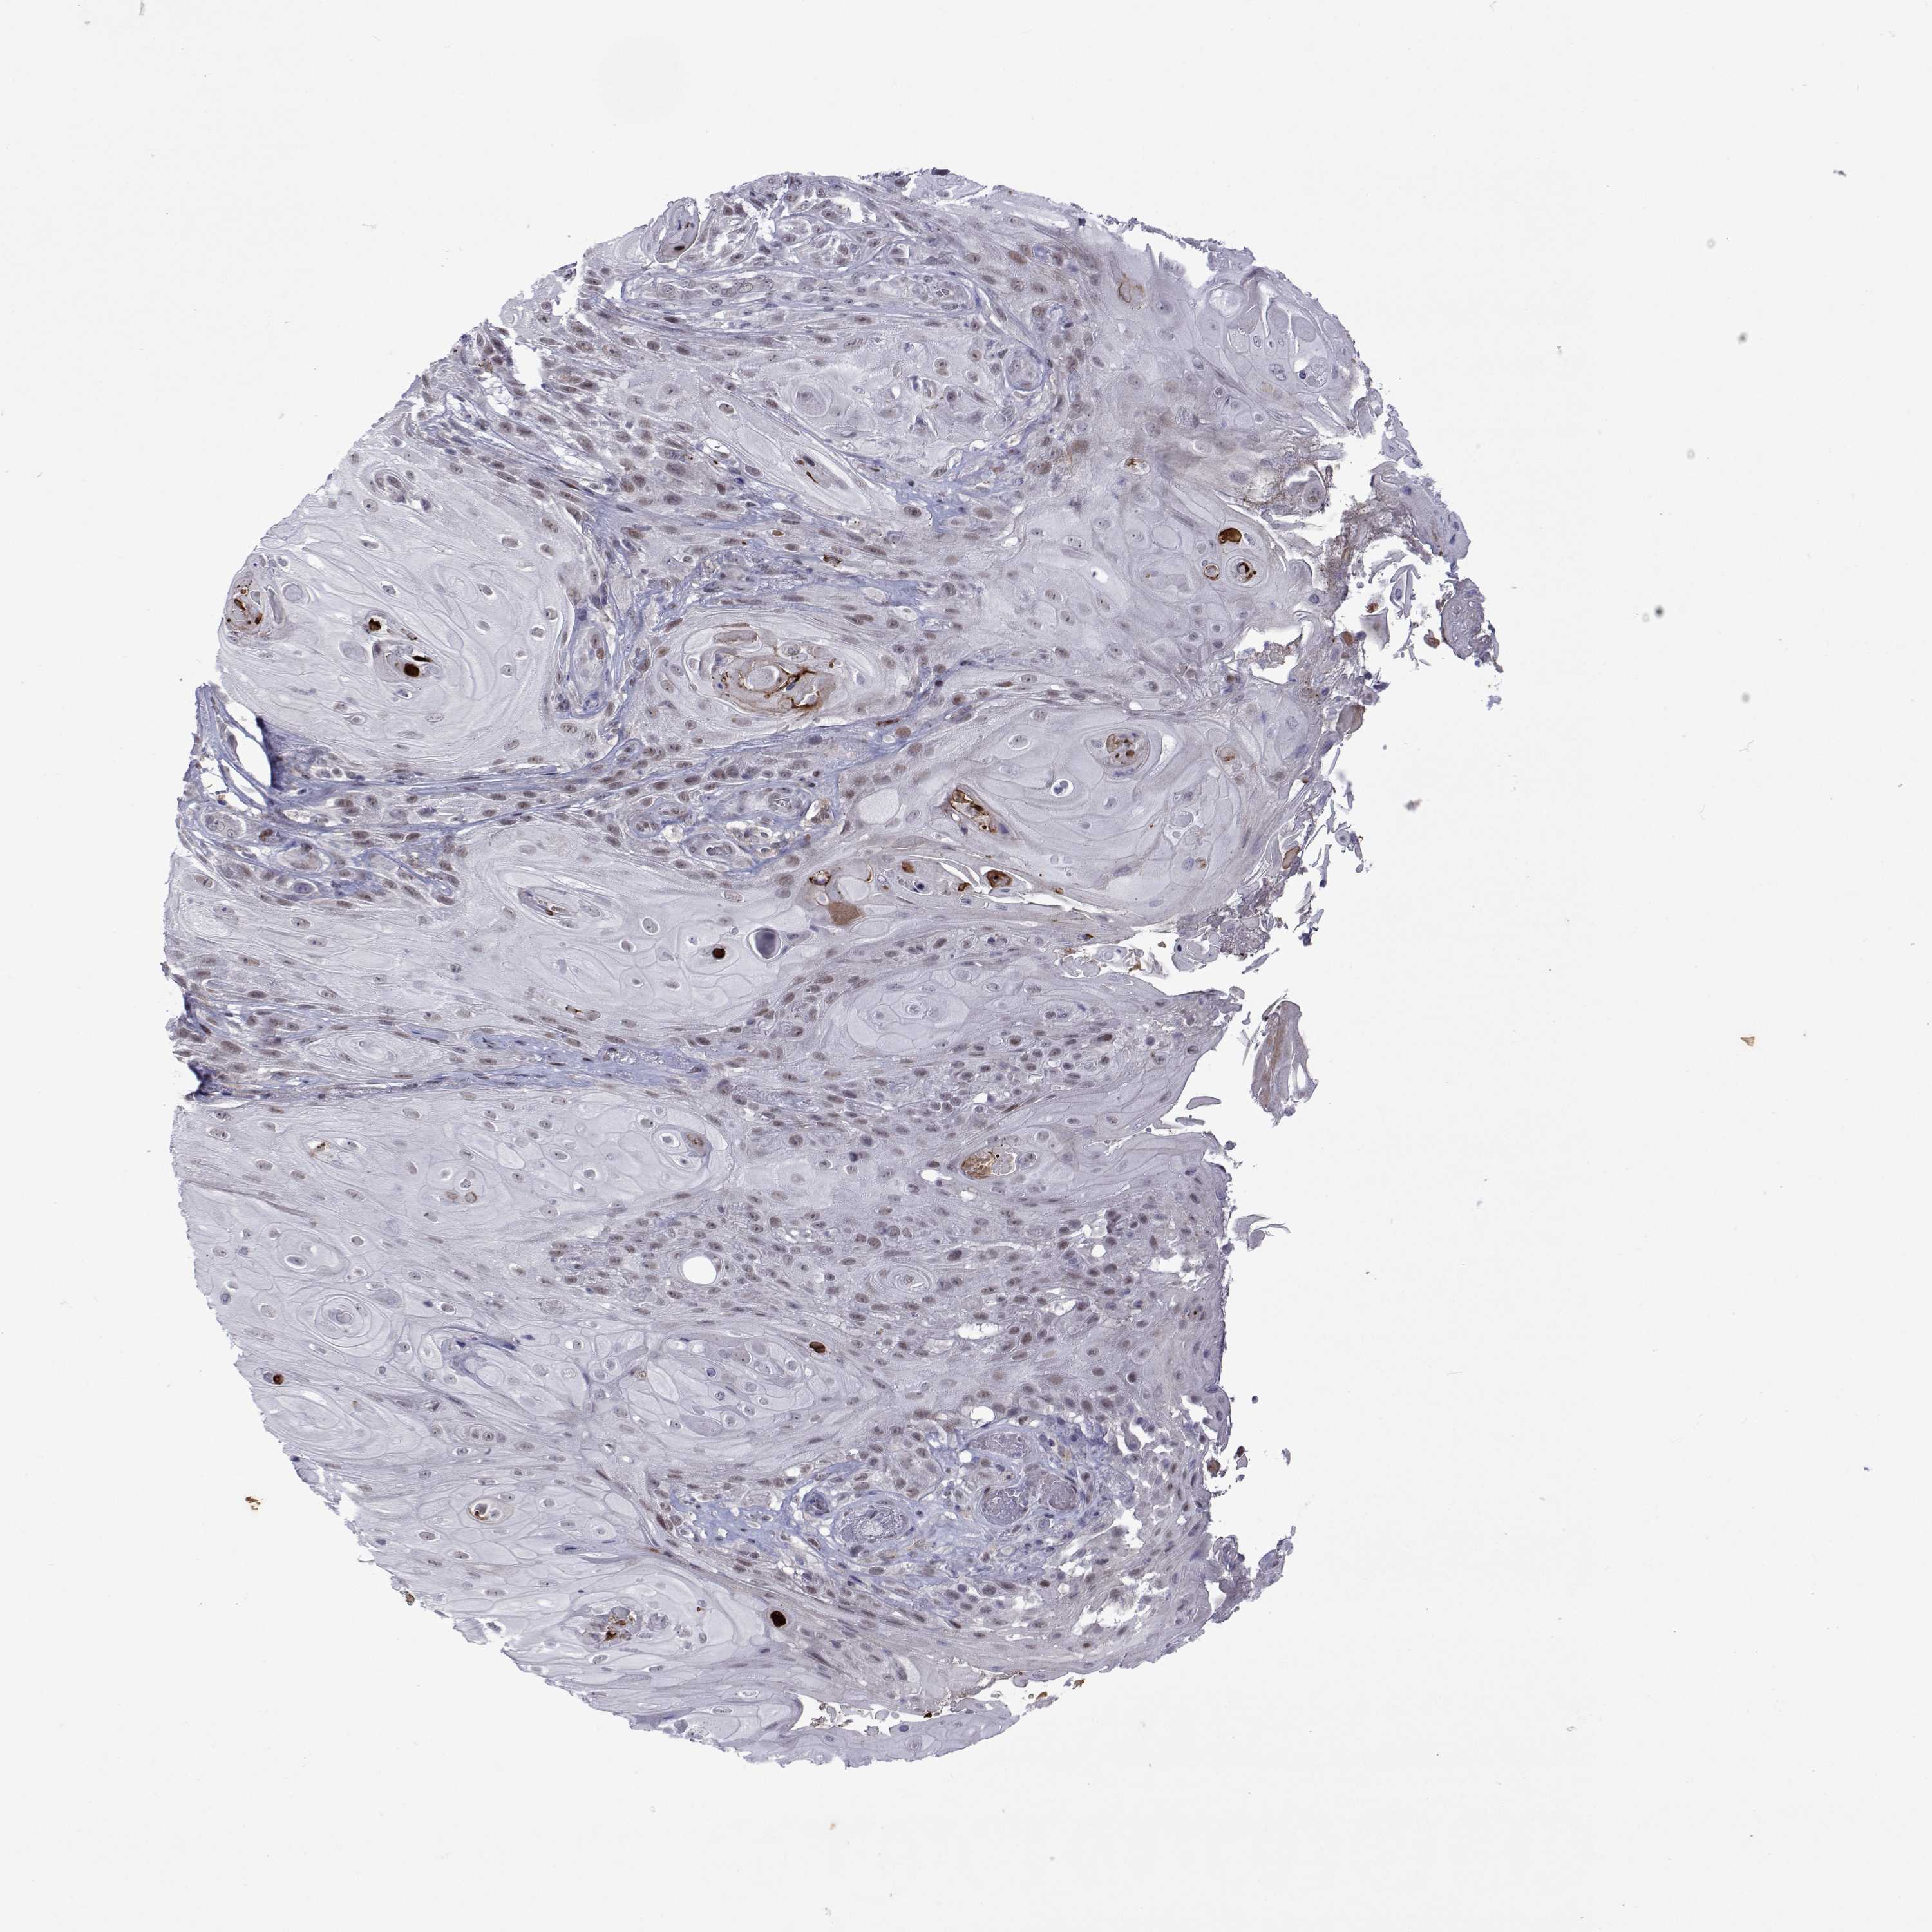

SKIN CANCER - Protein expressioni

A mouse-over function shows sample information and annotation data. Click on an image to view it in a full screen mode. Samples can be filtered based on level of antibody staining by selecting one or several of the following categories: high, medium, low and not detected. The assay and annotation is described here.

Each image is clickable and will lead to virtual microscopy that enables deeper exploration of all samples and also displays staining intensity scores, fraction scores and subcellular localization as well as patient and tissue information for each sample.

Antibody HPA046862

Staining

High

Medium

Low

Not detected

Intensity

Strong

Moderate

Weak

Negative

Quantity

>75%

75%-25%

<25%

None

Location

Nuclear

Cytoplasmic/membranous

Cytoplasmic/membranous,nuclear

Basal cell carcinoma

Squamous cell carcinoma, NOS